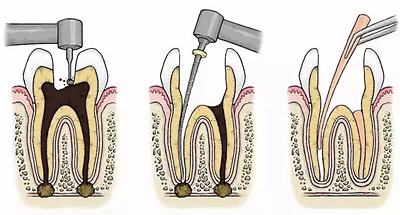

根管治療術(shù)又稱牙髓治療,是牙醫(yī)學(xué)中治療牙髓壞死和牙根感染的一種手術(shù)。該手術(shù)保留了牙齒,先是揭開髓室,頂敞開通路,用拔髓針拔除感染的牙髓。在用擴挫針擴凈根管壁,之后在根管內(nèi)封消炎藥,最后再用牙膠尖充填,手術(shù)繁瑣,一般要2-4次就診才能完成。隨著技術(shù)和材料的進步,活髓牙一次性根管治療術(shù),也在臨床應(yīng)用。

根管治療步驟

1.開髓:即將患牙打開,暴露髓腔。

2.根管預(yù)備:通過不同器械在牙根里面切削清理擴大根管。

3.沖洗消毒:對患牙充分沖洗、消毒滅菌,然后封消毒液一周。

4.根管充填:一般放置人工無菌材料,封閉腔體。

5.對牙冠方向的缺損進行填充修復(fù)。一般整個治療過程需要就診兩到三次,根據(jù)患者情況而定。